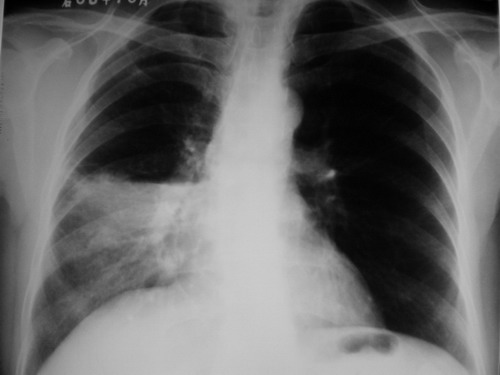

女,63,咳嗽,咳血1天,伴胸闷胸痛,查体未闻及干湿性罗音.

右中叶实变,侧位片示右上、下叶见斑点状阴影,结合病史,如是大叶性肺炎,应有发热。患者咳血,年龄较大,应警惕肿瘤,可是右肺门未见明显增大,周围见斑点影,还是先考虑结核。建议进一步纤支镜检查。

右中叶大叶性肺炎(右肺中叶实变,体积未见明显变化-叶间裂未见明显移位)请结合临床症状体征进一步分析;(咳血并非为结核或肺癌所特有)

右中肺野示一片状高密度影,上缘较清。侧位呈三角形,尖端指向肺门。考虑:右肺癌可能性大。

中间段支气管存在,肺体积未见明显缩小,所以应考虑右中叶大叶性肺炎。